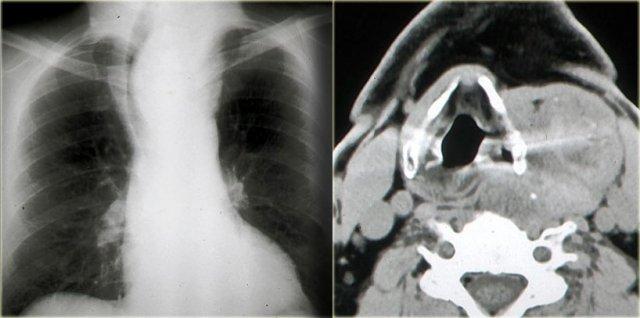

Bướu giáp đa nhân

Bước 1: Xác định khoang

Bên trái là hình ảnh một bệnh nhân có khối phồng ở bên trái cổ, đã tồn tại nhiều năm.

Khối phồng tiếp giáp với cánh sụn giáp bên trái.

Các cơ dây đai có vẻ như được trải phủ lên tổn thương (mũi tên xanh).

Do đó, tổn thương này nằm trong khoang tạng.

Bước 3: Nhận dạng hình thái và thông tin lâm sàng

Trên phim ngực, chúng ta nhận thấy khí quản bị đẩy lệch sang phải bởi một khối trung thất trên.

Vì vậy, khối nằm trong khoang tạng và lan rộng vào trung thất trước, do khí quản nằm trong trung thất trước.

Khối có bờ rõ nét so với mô mỡ xung quanh và có một vài vôi hóa thô rải rác.

Khi kết hợp các dấu hiệu này, chúng ta nhận ra hình thái học trên chẩn đoán hình ảnh của bướu giáp đa nhân lành tính.

Chẩn đoán này phù hợp với thông tin lâm sàng rằng khối phồng ở cổ đã tồn tại nhiều năm.